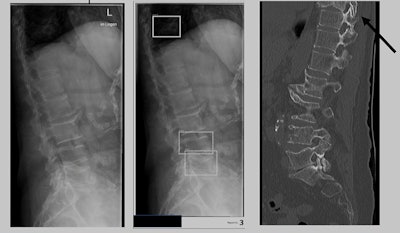

Oppenheimer and colleagues included lumbar spine radiographs from 60 osteoporotic patients with suspected fractures. The presence and Genant grade of fractures (1-3 by percentage of height loss) was defined by written reports by a radiologist with eight years of experience in muskuloskeletal imaging. The x-ray images were then analyzed by the AI software, which identified vertebras as definitely or likely fractured, and a per vertebrae comparison of AI classification to Genant grade was performed.

Thirty patients had at least one fracture, with a total of 62 vertebral fractures in 435 analyzed vertebrae. Thirty fractures were labeled by the radiologist as Genant grade 1, 20 were grade 2, and 12 were classified as grade 3. For detecting and classifying these fractures, the overall sensitivity of the algorithm was 79%, with a sensitivity of 66.7% for grade 1, 90% for grade 2, and 91.7% for grade 3. The specificity of the algorithm was 96%.